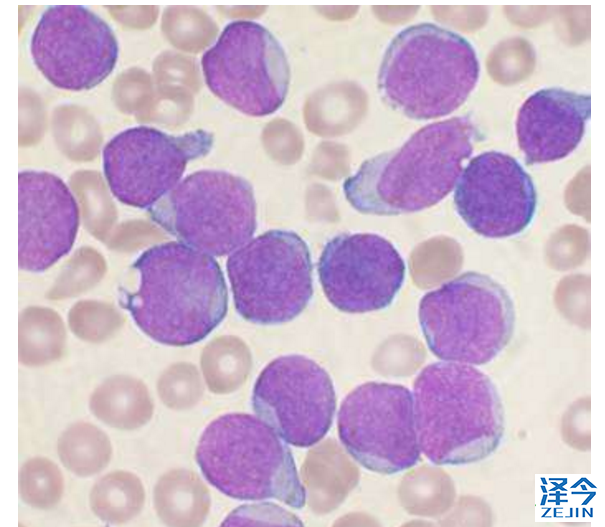

1、世纪之争终于尘埃落定!科学家首次发现儿童白血病诱因

最新研究首次揭示了儿童白血病可能的原因,这是一个经历了一个多世纪的争议。急性淋巴细胞白血病在当今社会特别普遍,发病率每年约增加1%。

伦敦癌症研究所的Mel Greaves教授评估了有史以来收集的急性淋巴细胞白血病(ALL)最全面的证据。得出结论,这种疾病是由基因突变和接触感染两个步骤引起的,这意味着在婴儿期可以通过治疗来刺激或激活免疫系统。

第一步涉及胎儿出生前发生的基因突变,并使儿童易患白血病,但只有1%的患有此遗传改变的儿童会继发为白血病。第二步也很重要。这种疾病后来在儿童时期通过接触一种或多种常见感染而被触发,在一岁之内没有任何异常发生,而与其他婴儿或较年长的儿童没有太多区别。

Greaves教授质疑过去有关可能的环境原因的报道,如电离辐射、电缆、电磁波或人造化学物质,因为没有强有力的证据支持这些是主要原因。相反,他提出了强烈的证据来证明ALL病因的“延迟感染”理论,其中早期感染有利于激活免疫系统,但是没有早期激活免疫系统的情况下感染可能引发白血病。

如果婴儿在一岁之内免疫系统被适当地激活,儿童白血病、I型糖尿病、其他自身免疫疾病和过敏等可能都是可以预防的,使儿童免受创伤和化疗的终身影响。

我希望这项研究将对儿童的生活产生真正的影响,或许可以通过简单安全的干预措施将婴儿暴露于各种常见和无害的免疫原中激活免疫系统,未来儿童白血病可能成为可预防的疾病。